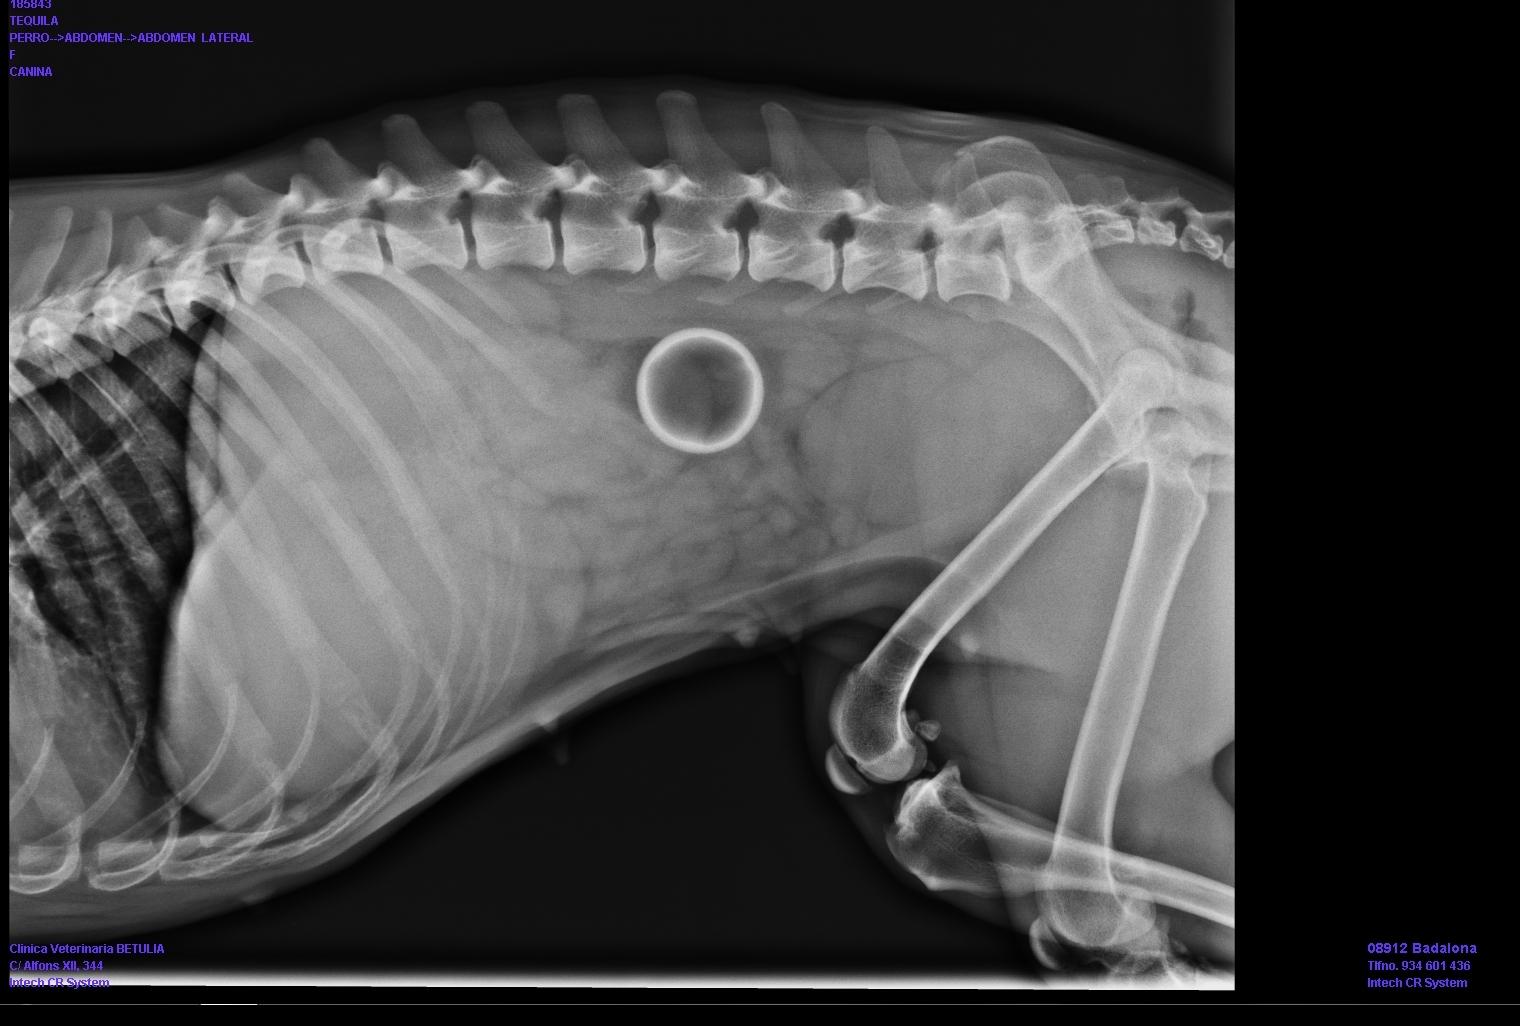

¿Qué hacer en caso de obstrucción intestinal en perros? Para detectar una obstrucción intestinal en perros el veterinario puede hacer una radiografía del abdomen. En ella se puede apreciar la distensión en los intestinos y una gran cantidad de gas. Aun así, jamás se debe medicar a un perro con síntomas sin diagnóstico veterinario ya que podría resultar contraproducente e incluso mortal.

En algunos casos el veterinario puede realizar una exploración digestiva mediante endoscopio. A veces con este procedimiento es posible resolver la obstrucción, como las causadas por cuerpos extraños, al conseguir extraer el objeto que la produce. Además, si algún fragmento del intestino está dañado el veterinario tendrá que extraerlo.